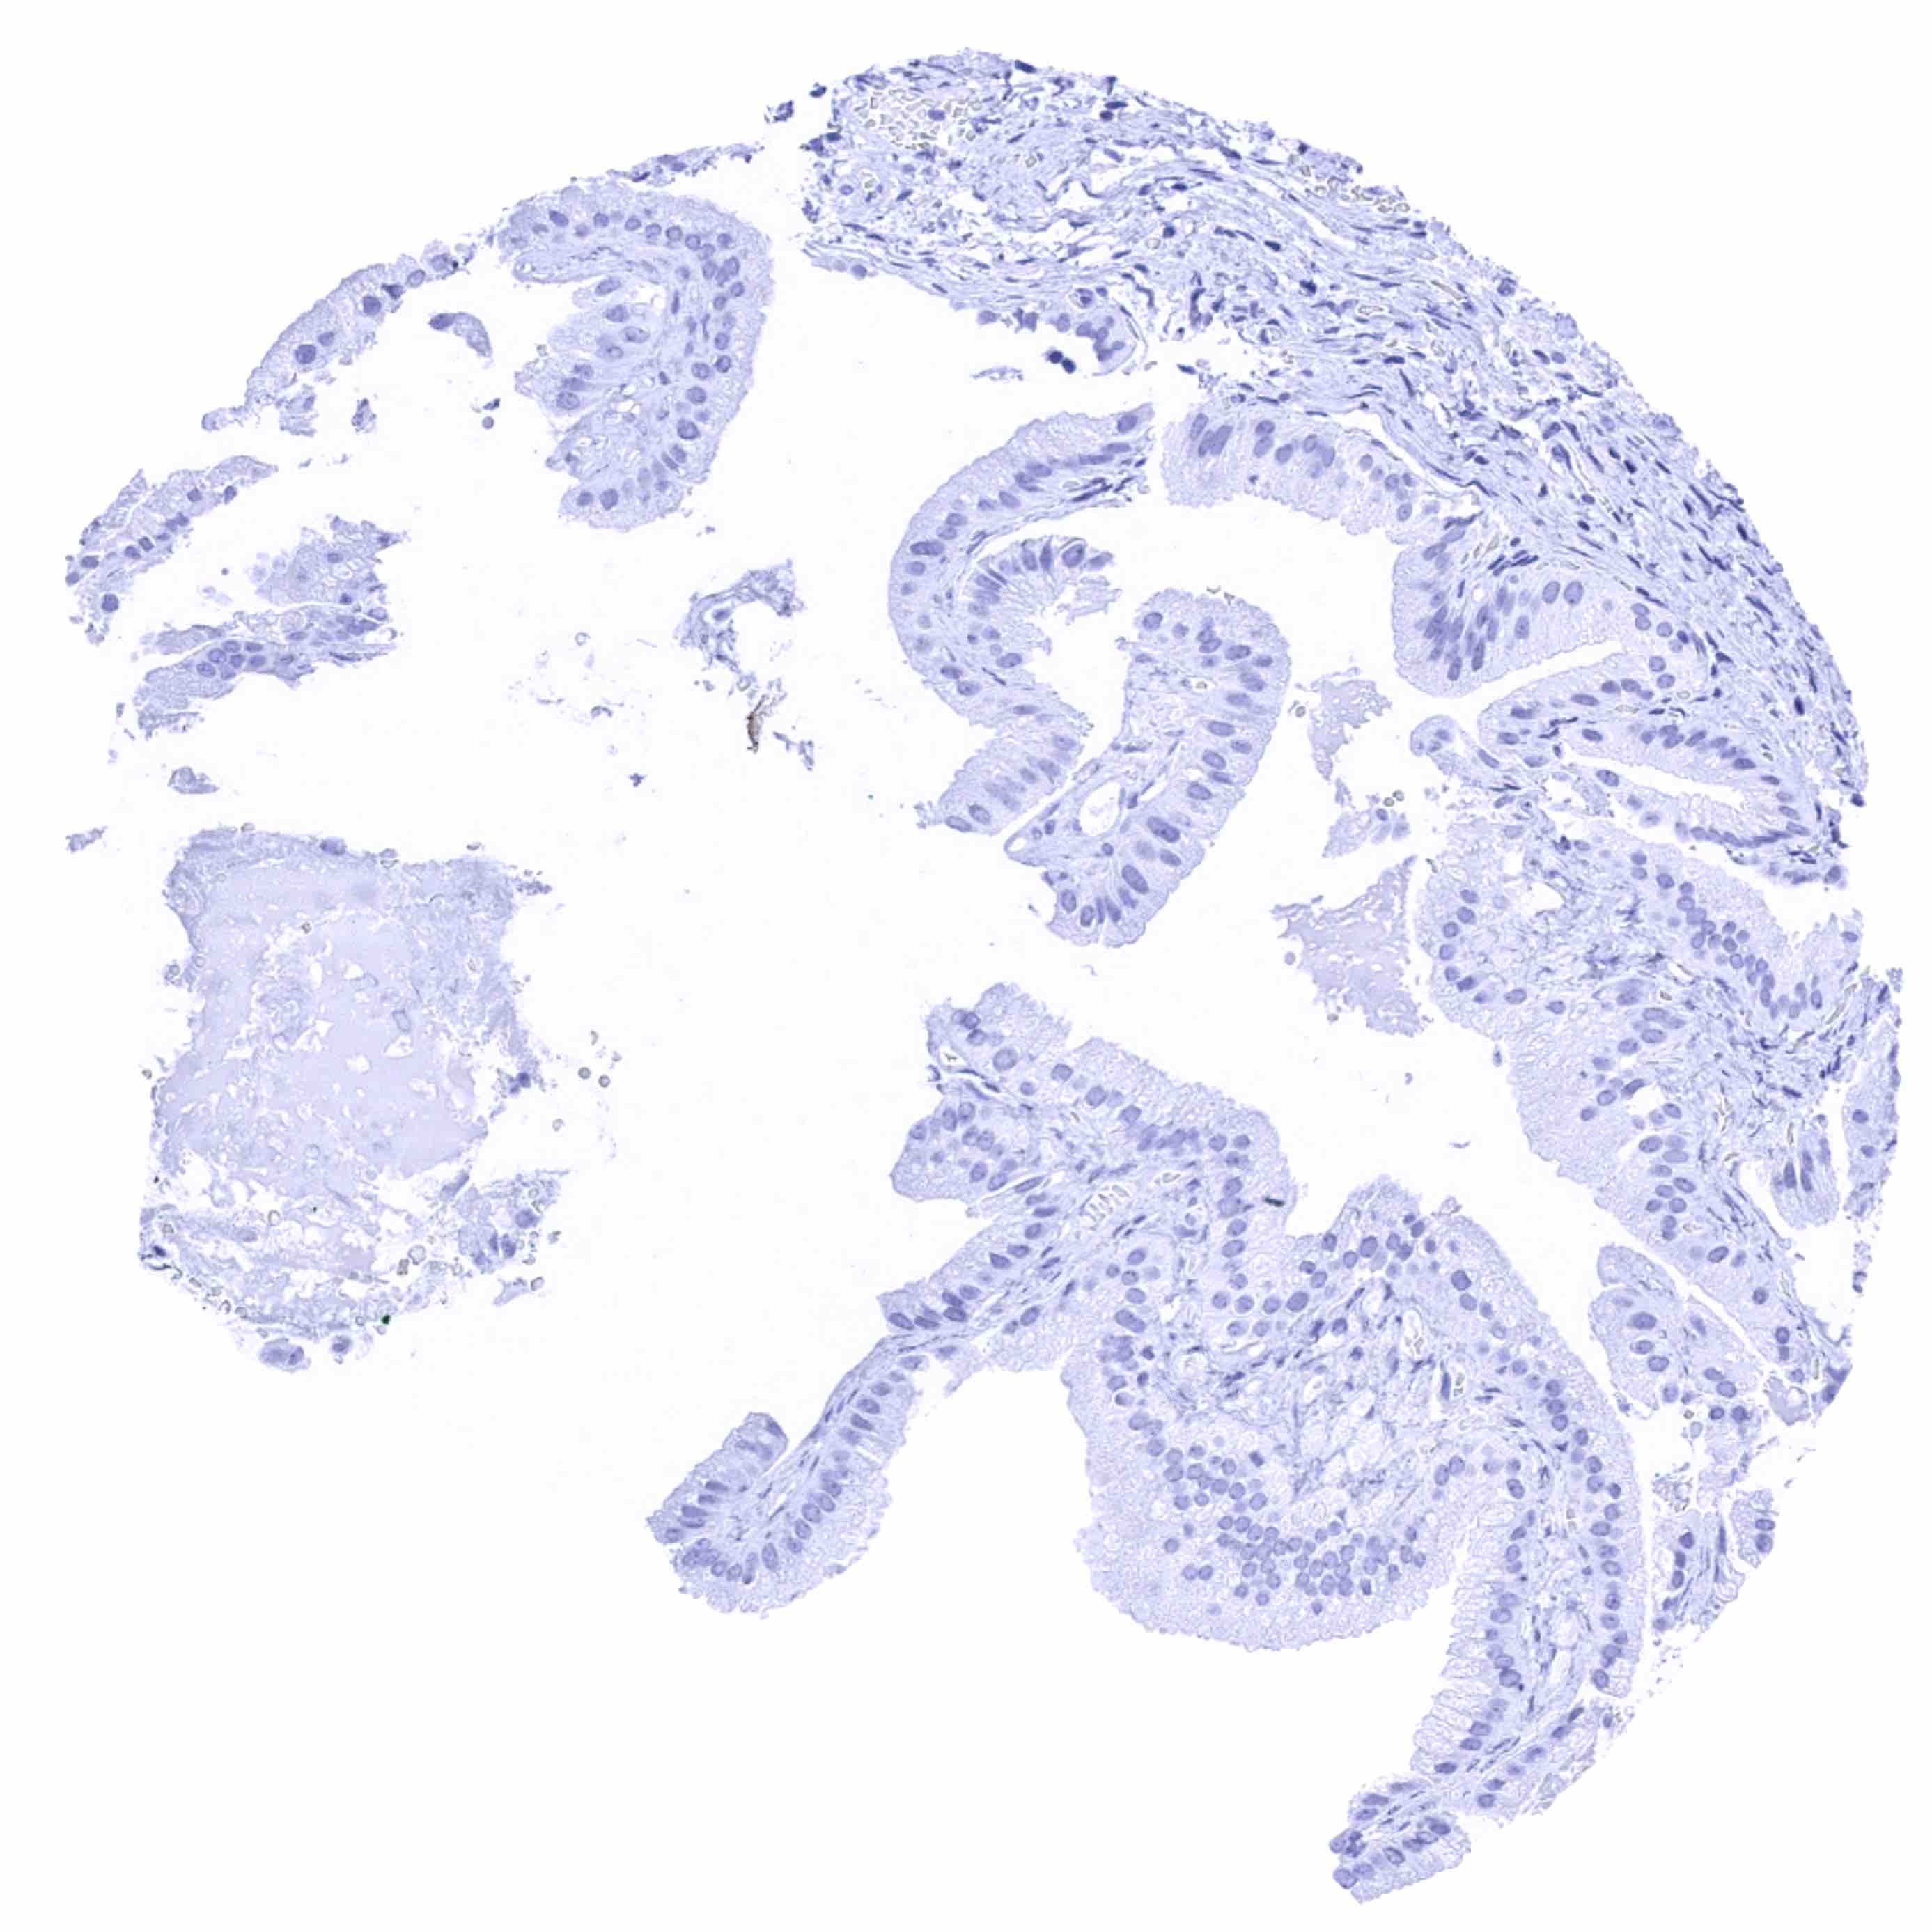

Duodenum, mucosa

Duodenum, Brunner gland